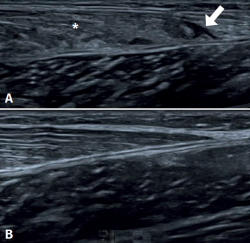

Ultrasound is the initial imaging technique of choice, due to its rapid accessibility, low cost and the absence of radiation(26,27,28), as reflected in Figure 1. Some of the features to be evaluated by ultrasound are the size of rupture, whether rupture is total or partial, and the presence of haematoma and/or fluid collections between the gastrocnemius and the soleus.

Figure 1. Ultrasound study of triceps surae injuries. A: fibrillar damage of the distal myotendinous junction of the medial gastrocnemius muscle, showing the hypoechogenic fibrillar defect (arrow) associated to loss of the usual fibrillar pattern and oedema of the adjacent muscle fibres (asterisk); B: distal myotendinous junction of the medial gastrocnemius in a normal triceps surae muscle.

The most frequent ultrasound finding in triceps surae muscle injuries is a hypoechogenic zone at the distal myotendinous junction of the medial gastrocnemius muscle(29). The latter appears as a serohematic content between the muscle fibres and the myofascial plane, associated to an increase in echogenicity of the adjacent musculature as a manifestation of oedema and hyperaemia in the colour Doppler study(9), as can be seen in Figure 1. Delgado et al., in 141 patients clinically diagnosed with tennis leg, found that 67% of the patients presented partial rupture of the medial gastrocnemius, 1.4% presented associated plantaris tendon rupture, and 21% presented an intermuscular fluid collection between the medial gastrocnemius and the soleus muscle - thus affording an improved perspective of the possible differential diagnosis(30). On the other hand, involvement of the lateral gastrocnemius is much less common (up to 14% of the cases)(31). Ultrasound also plays a role in the lesions follow-up. In a normal evolutive scenario, we can observe gradual reduction of the oedema, resolution of the fibrillar defect and reabsorption of the fluid collections(32). It is also common to observe signs of organization of the haematoma between the gastrocnemius and the soleus, evolving as a fusiform fibrous scar without inflammatory elements, as can be seen in Figure 2.